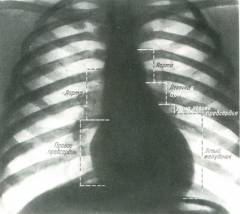

Рентгенологическое исследование

Рентгенография позволяет увидеть изменения в легочной артерии и правом желудочке, а также другие признаки легочного сердца.

При хроническом легочном сердце на рентгенограмме могут наблюдаться:

- увеличение легочной артерии (ее дуга лучше видна в косой проекции);

- увеличение правого желудочка;

- округлая форма сердца;

- сужение средостения;

- расширение корней легких (признак легочной гипертензии);

- усиление легочного рисунка или новообразования в легких (признаки заболеваний, приведших к легочному сердцу).

Рентгенологическое обследование использует минимальные дозы радиации. Оно не рекомендуется для детей и беременных женщин. Остальным пациентам следует проводить исследование один раз, избегая повторных облучений и используя альтернативные методы диагностики.